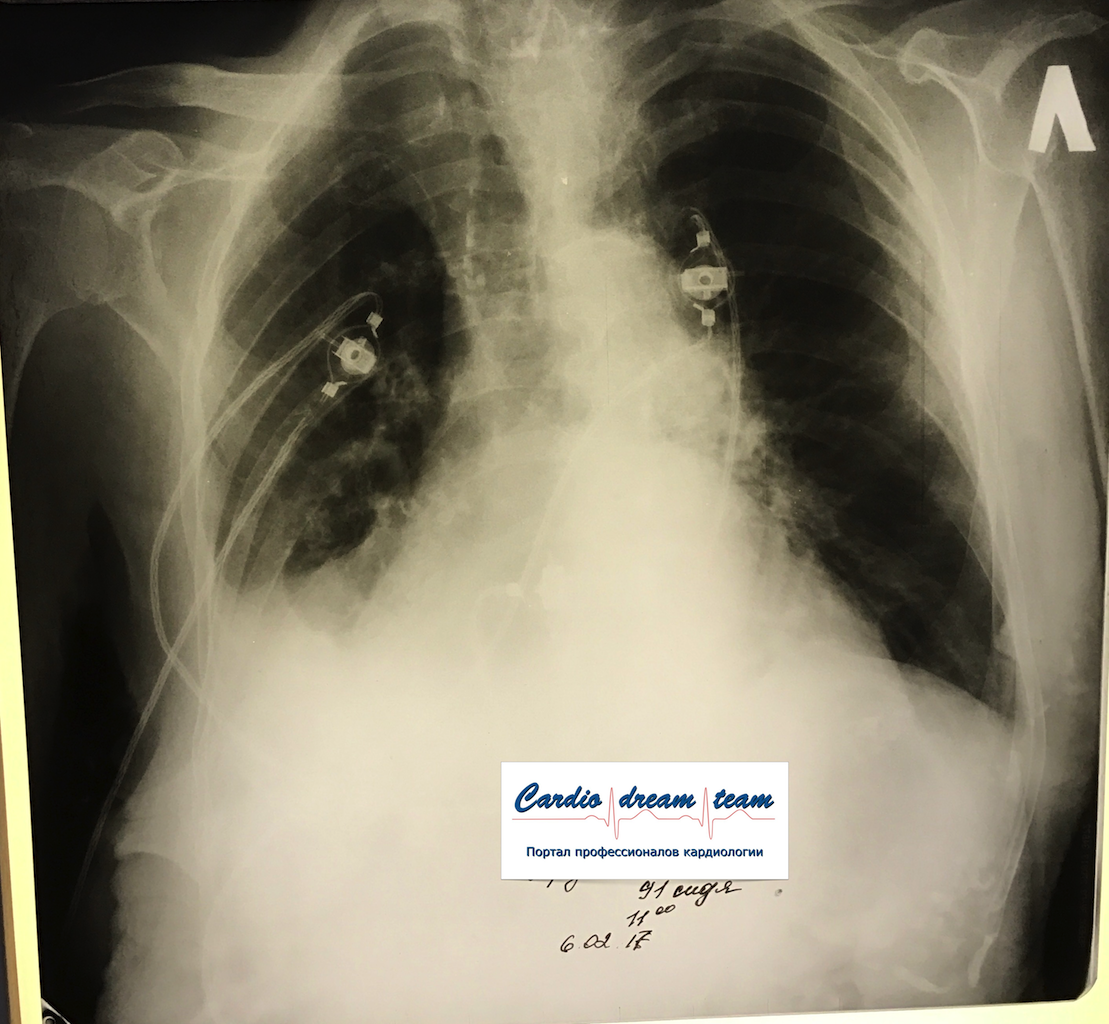

Гидроторакс. Серия снимков.

1 - лежа. Так делать не надо! Надо только сидя!

2 - сидя. Понятно, что гидроторакс за раз не победить

3 - удалено 1100.

4 - удалено ещё 1200. И диуретики все эти дни.